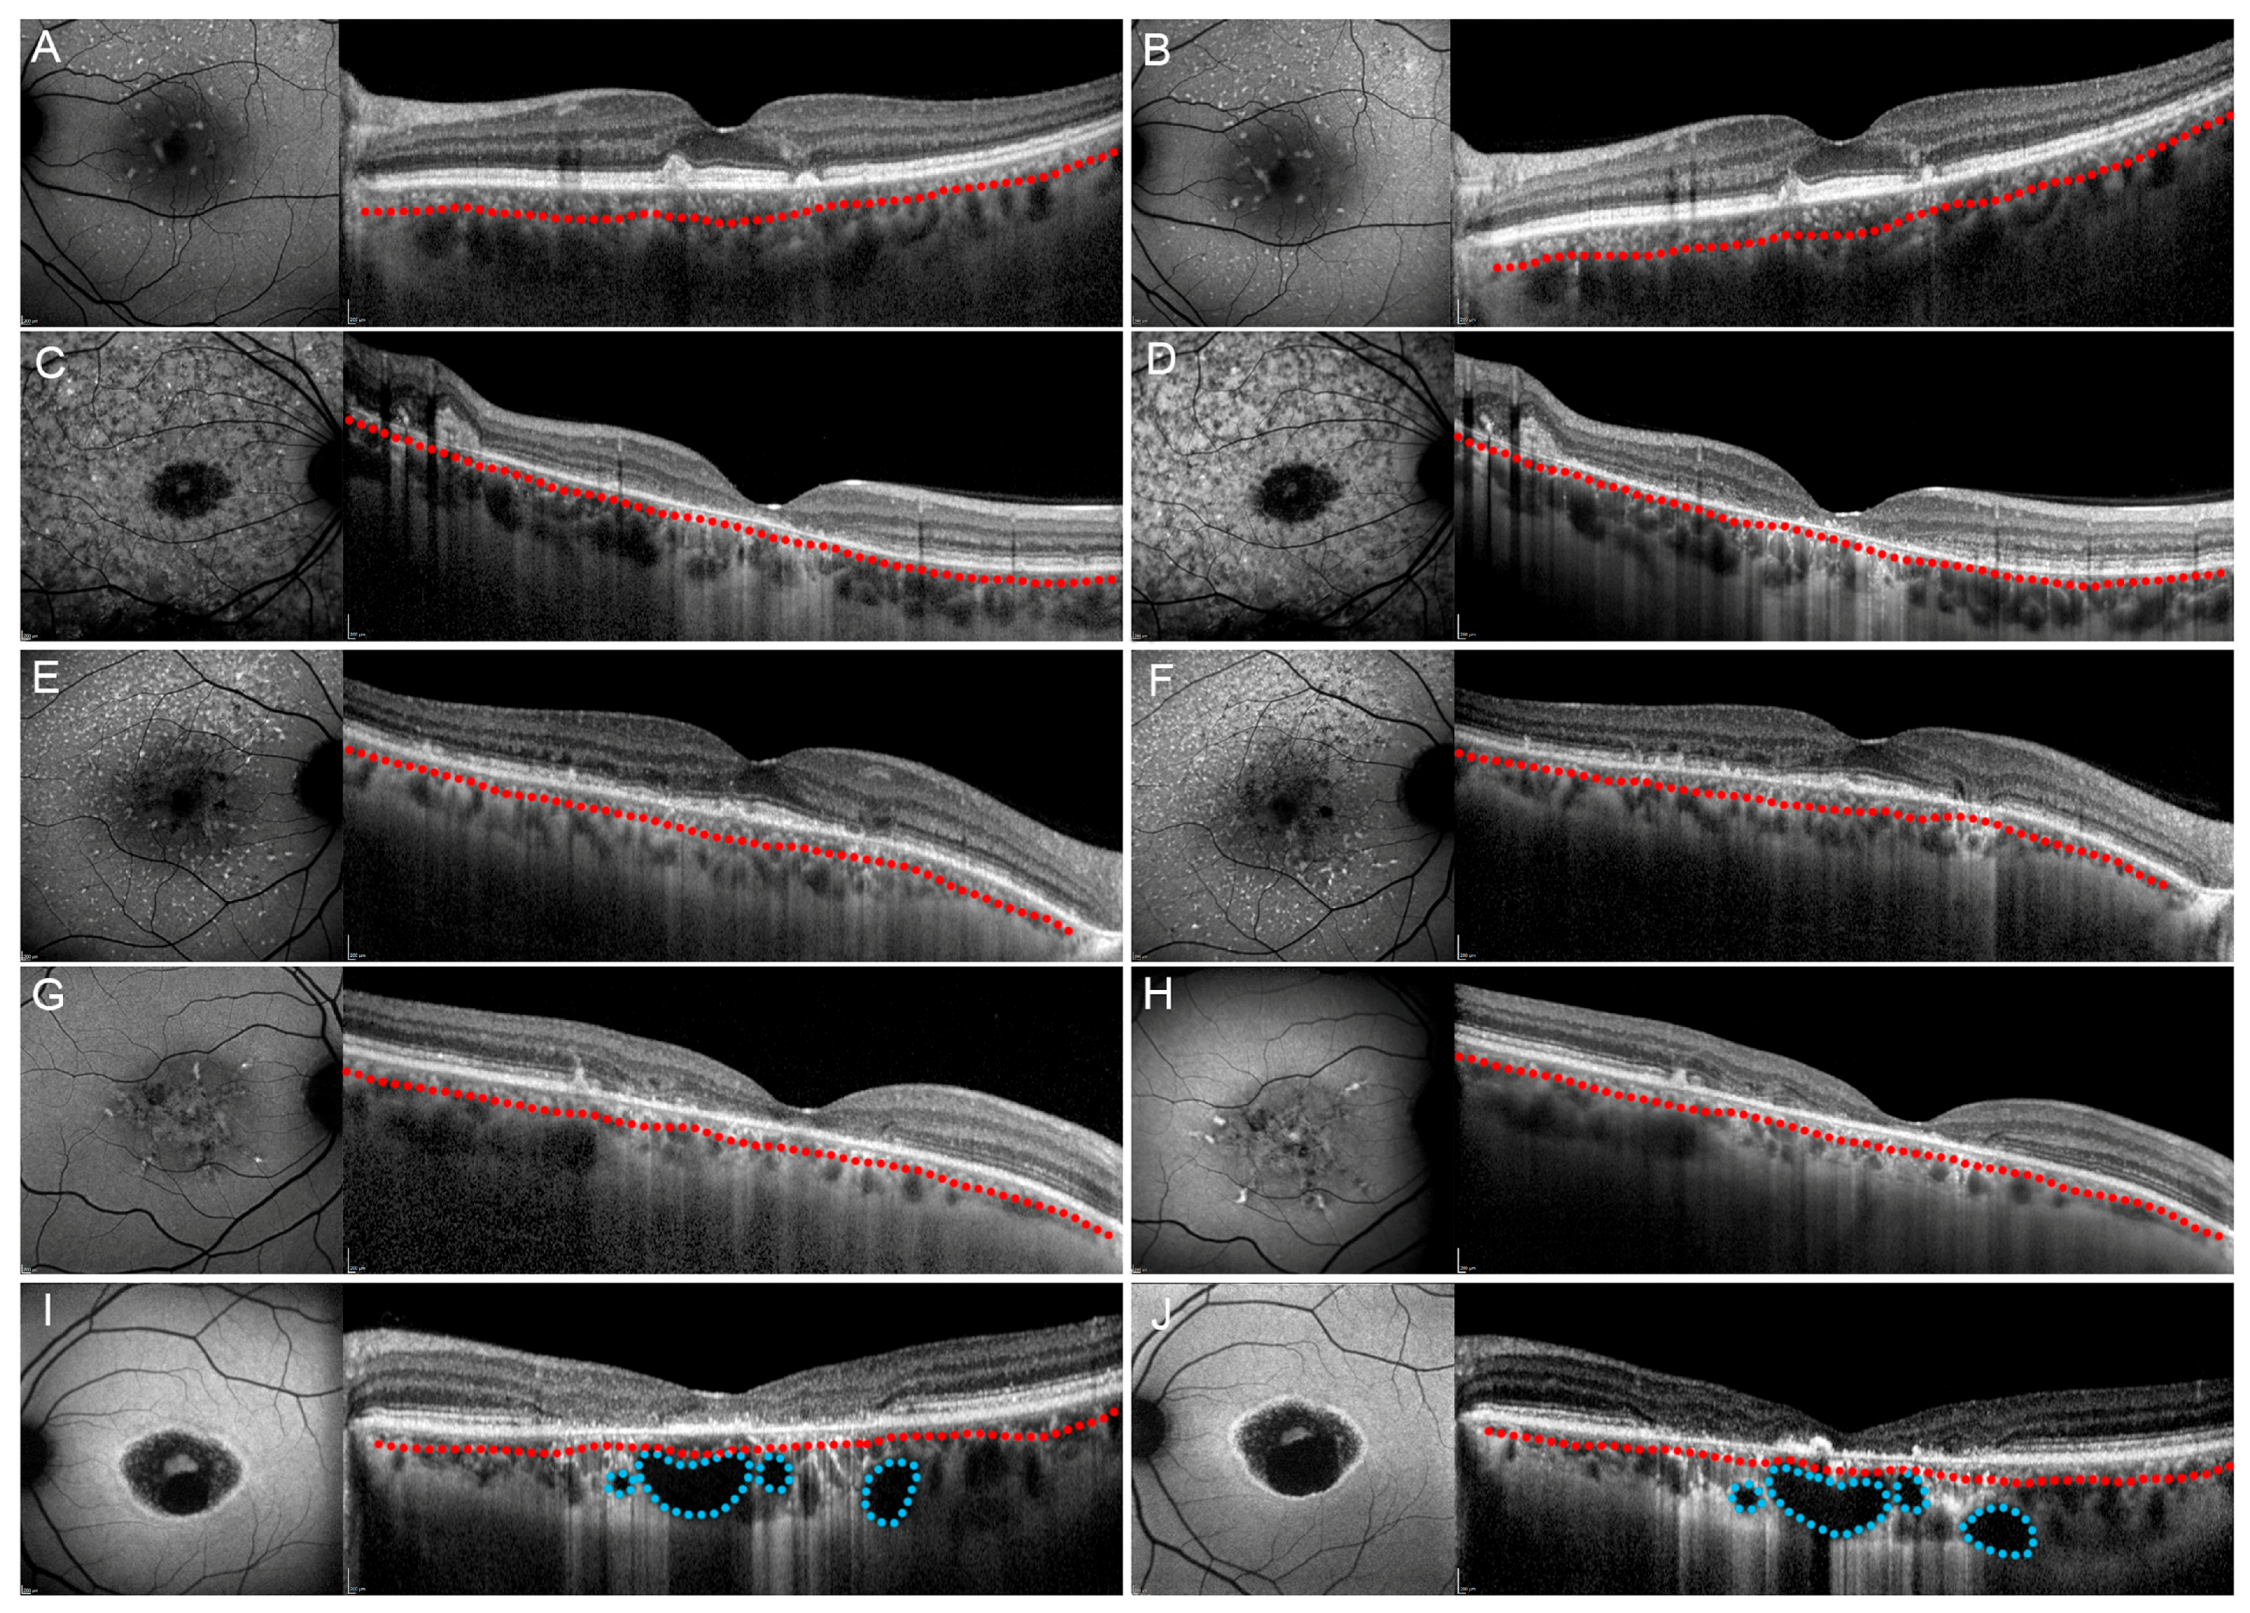

After one year of follow-up, our patients’ subgroups showed different progression features. All patients maintained the same choroidal pattern found at baseline. Pattern 1 and Pattern 2 showed unremarkable functional and anatomical changes (all p > 0.05) (Figure 3). Pattern 3 and Pattern 4 revealed significant structural and functional deterioration over the one-year follow-up (Figure 3). Overall, BCVA tended to decrease over the one-year follow-up, together with the worsening of structural OCT and OCTA parameters. All the quantitative parameters are shown in Figure 4. Moreover, all values are extensively reported in Table S3.

Figure 3. Stargardt disease progression after one year. Fundus autofluorescence-FAF is shown on the left and structural optical coherence tomography-OCT is shown on the right parts of each image. Pattern 1 (A,B), Pattern 2 (reduced Sattler layer) (C,D) and Pattern 2 (reduced Haller layer) (E,F) showed unremarkable changes both on FAF and structural OCT after one year, followed by unremarkable changes of best corrected visual acuity (BCVA). On the contrary, Pattern 3 (G,H) and Pattern 4 (I,J) showed both imaging and BCVA worsening after one year. In all images, Sattler and Haller layers are separated by a red dotted line. Moreover, choroidal cavers are highlighted by blue dotted lines.